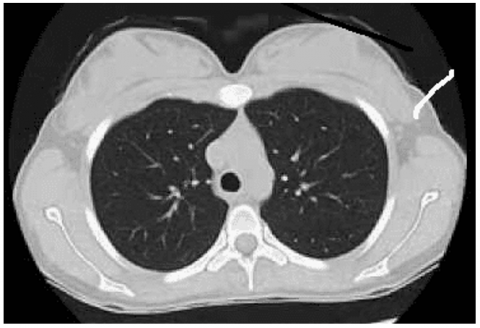

The first stage of the developed framework is the lung CT image acquisition from both healthy and cancer-affected persons as shown in Figure 2. The gathered images are labeled to train the classifier to recognize the patterns of lung cancer. The presented study used the publicly available Lung CT scan database from Kaggle site [27].

Figure 2. Dataset images of different classes: (a) Lung cancer; (b) Normal